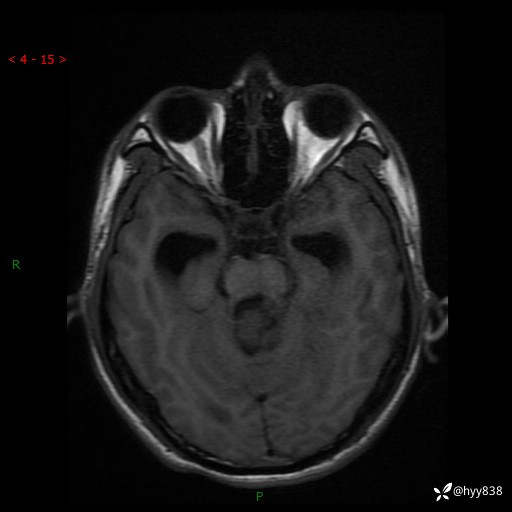

性别:男

年龄:17岁

简要病史:头痛伴间断性呕吐1月余,外院CT提示颅脑占位

颅脑MRI平扫+增强